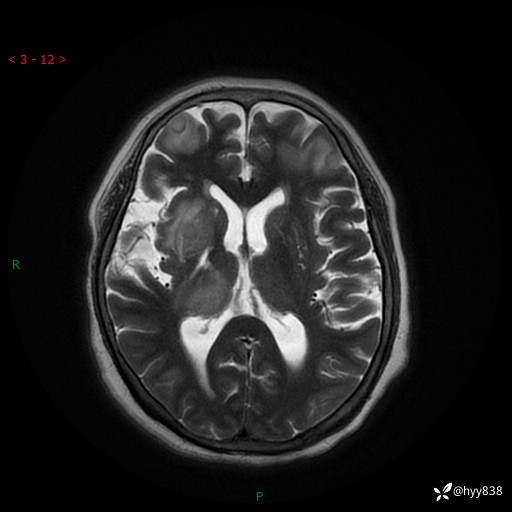

颅脑MRI(T2WI+DWI)